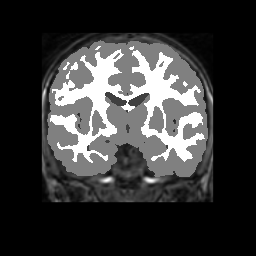

Accuracy is reported as Dice overlaps between a tool's segmentation and the Internet Brain Segmentation Repository (IBSR) manual segmentation for each of the 18 IBSR subjects. The inter-tool comparison (on the left below) shows the median Dice coefficient for each tissue class. The overlaps for FSL (from which the median values are drawn) are shown in the plot on the right.

Subject Accuracy (IBSR)

Overlap coefficients for each tissue class are shown here for each IBSR subject. Select a subject below to see the FSL results compared to other tools.